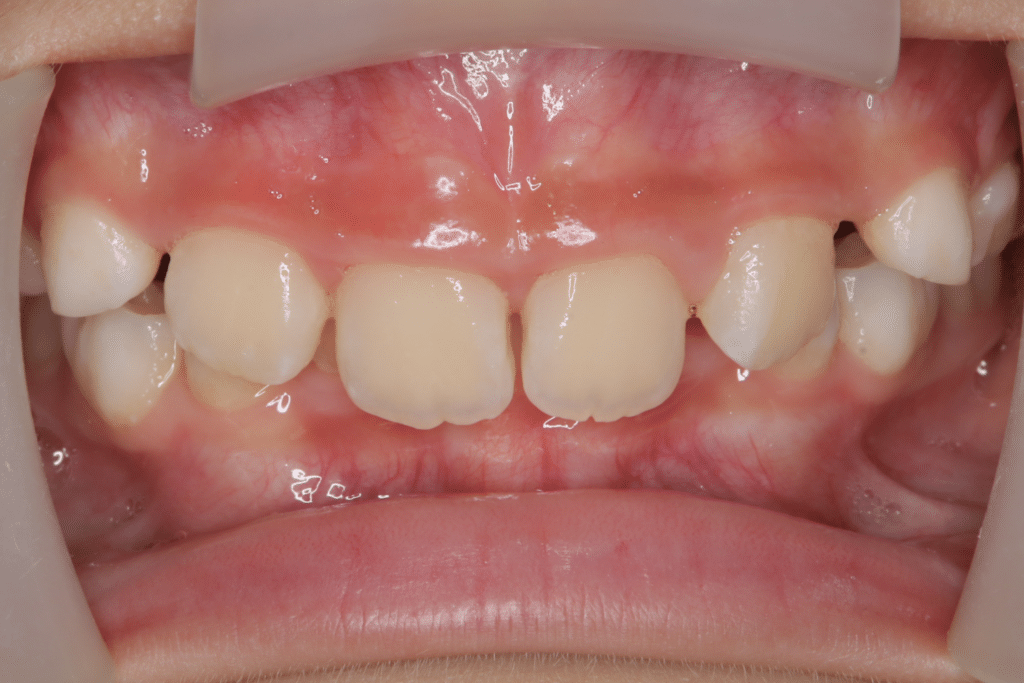

主訴:前歯の噛み合わせが深くて、奥歯の歯が隠れてしまっている。歯ぎしりもひどいのでそれも含めて改善したい

診断名:過蓋咬合(かがいこうごう)

(開始後0ヶ月)噛み合わせの深さからくる咬合圧の強さと歯ぎしりを心配されていたため、歯ぎしりから歯を守りつつ、噛み合わせの深さを改善するためのマウスピースを使用開始。

過蓋咬合

(9歳2ヶ月)

開始後0ヶ月